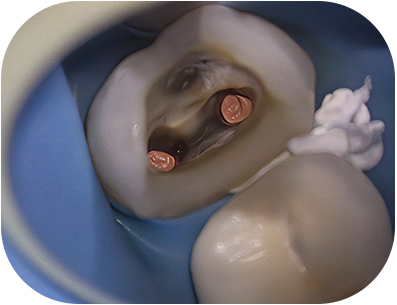

État initial d’une prémolaire

prémolaire, le composite présente une étanchéité insuffisanteFig. 01 : Ie composite présente une étanchéité insuffisante, notamment avec la reprise

d’une lésion carieuse en distal.

Nous avons choisi de réaliser la dépose intégrale des éléments coronaires afin d’accéder aux canaux, mais surtout d’augmenter nos chances de détecter et de traiter d’éventuelles fêlures ou caries secondaires(1).